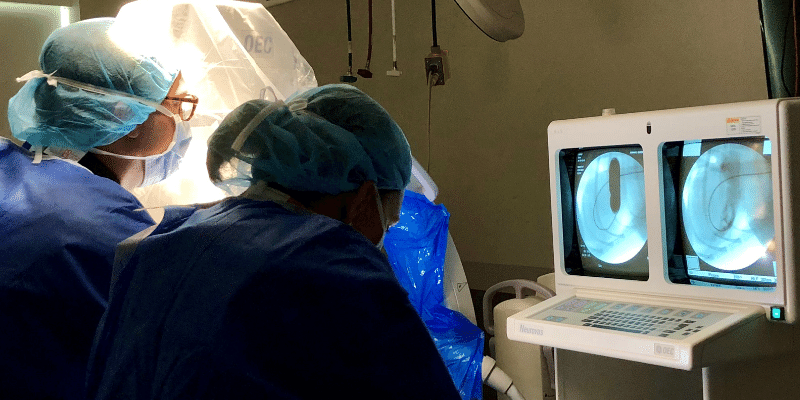

Our Cardiology Service performing a balloon valvuloplasty on a dog under fluoroscopic guidance.